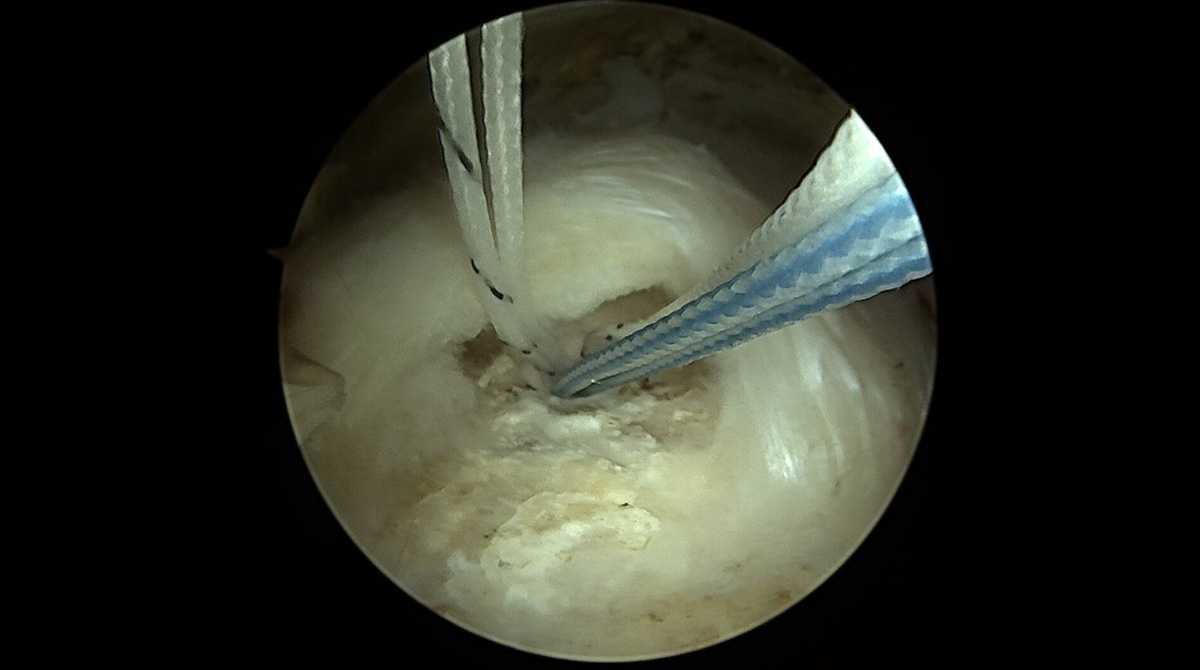

Cette intervention est actuellement réalisée sous arthroscopie, c’est-à-dire en rentrant une caméra et des instruments dans l’articulation de l’épaule par de petites incision centimétriques.

De multiples gestes peuvent être réalisés par cette technique. Les gestes réalisés dépendront du type et de la localisation de la rupture. Le but est de réinsérer les tendons abimés sur leur tubérosité. Cette réparation se réalise grâce à des systèmes de fils montés sur des ancres qui sont fixés dans l’os.